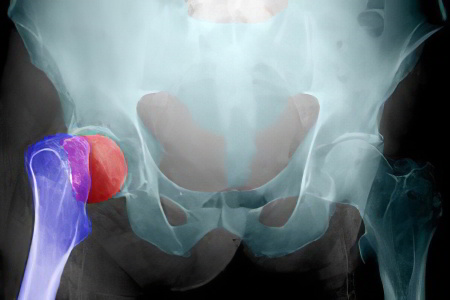

Переломы

Одним из наиболее распространенных типов переломов, вызывающих дискомфорт в области тазобедренного сустава, является перелом шейки бедренной кости.

Асептический некроз головки бедренной кости

Перелом шейки бедра чаще встречается у пожилых женщин, тогда как асептический некроз головки бедренной кости обычно затрагивает молодых мужчин. Наибольшее количество случаев наблюдается в возрасте от 20 до 45 лет.

Асептический некроз